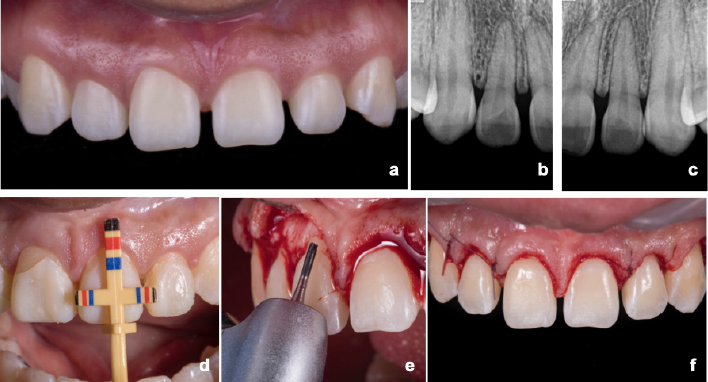

Paciente femenina de 21 años de edad, acudió a valoración dental para mejorar la estética dental, debido a que no le agradaban los espacios entre los dientes del sector anterior maxilar. El examen clínico inicial incluyó: el análisis del esquema oclusal (verificación de ausencia de interferencias posteriores en relación céntrica con Leaf Gauge), se verificó la oclusión mutuamente protegida, la cual no requería alteración, radiografías dentoalveolares y un protocolo fotográfico. Adicionalmente, el examen clínico reveló línea media desviada a la derecha con un plano incisal levantado del lado izquierdo, diastemas entre los dientes 13 al 23 con pequeñas zonas de atrición incisal en 21 y 11 (Figura 1. a-c). Se valoró el fonema “S” para determinar la posición del borde incisal y establecer las proporciones dentales, así como la posición de los niveles gingivales.

Figura 1 Caso inicial y alargamiento de corona. a. Fotografía inicial. b. Radiografía dentoalveolar izquierda. c. Radiografía dentoalveolar derecha. d. Mediciones prequirúrgicas. e. Procedimiento quirúrgico. f. Sutura.

Antes de iniciar el procedimiento quirúrgico se le pidió a la paciente que realizara enjuagues bucales con gluconato de clorhexidina al 0.12% durante 1 min y se desinfectó la región extra-bucal con Iodopovidona. Luego, se anestesió de manera local de los dientes 13 al 23, para hacer incisiones a bisel interno e intrasurcales. Se elevó un colgajo de espesor total respetando la posición y la altura de las papilas interdentales. La ostectomía varió de 1 a 2 mm. Posteriormente, se continuó con la osteoplastía y se adaptó el colgajo mucoperióstico con puntos suspensorios coronales y puntos simples; se suturó con ácido poliglicólico 6-0 (Figura 1. d-f).